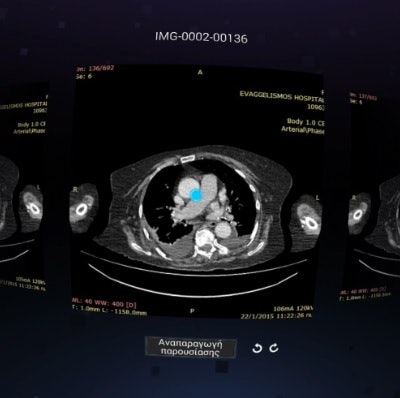

Remote interpretation of imaging studies often means using a mobile device with a small screen. But virtual reality technology can overcome those limitations and offer an immersive image viewing environment without sacrificing image quality, Greek researchers reported at RSNA 2015 in Chicago.

After modifying virtual reality hardware and software to be able to support the viewing of DICOM images, a team from Evangelismos Hospital in Athens found it could produce more than 97% interobserver agreement in testing on 271 CT studies.

"Remote diagnosis of complete CT examinations performed elsewhere using our mobile virtual-reality [device] is feasible and useful," presenter Dr. Vasileios Moustakas said.

"[The results show that] the use of our virtual-reality device did not affect image quality and therefore, did not alter the diagnosis," Moustakas said. "This technique can be used for remote diagnosis while avoiding the small-display limitations."